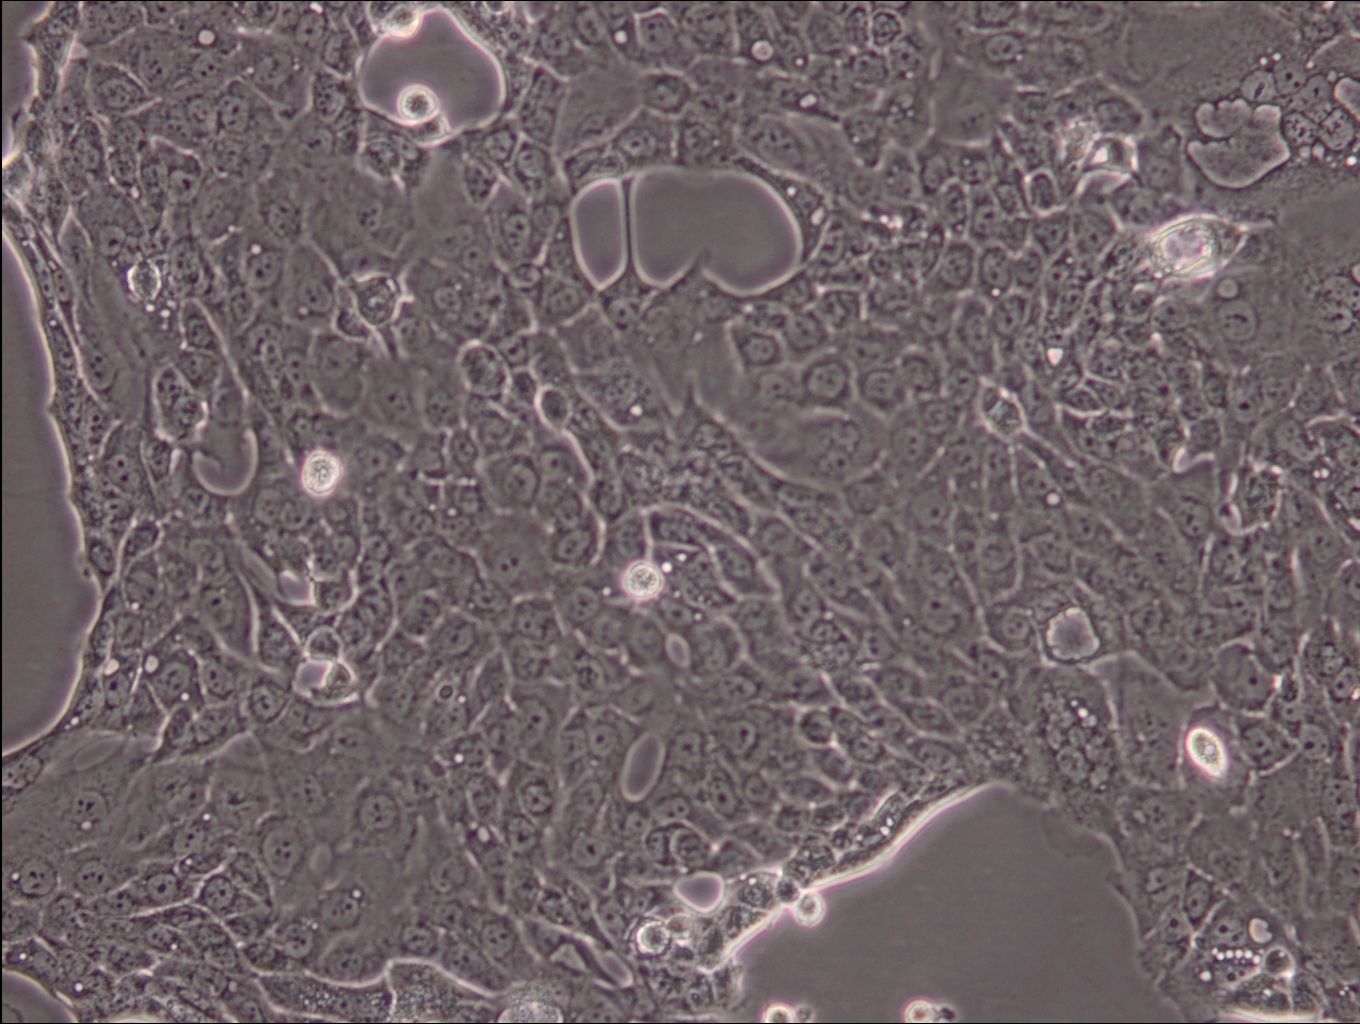

CFPAC-1是胰腺管腺癌細胞系,建自26歲白人男性囊性纖維變性(CF)的肝轉移灶。 該細胞系表達囊性纖維變性跨膜調節因子(CFTR)。 形態為上皮樣且頂端微絨毛極化。該細胞表達胰腺管細胞特征性的細胞角蛋白和癌胚抗原。倍增時間為30-32小時。 它是亞3倍體的細胞系,36%的細胞的染色體模式數為75。 該細胞傳代至24代時在無胸腺小鼠中致瘤 |

形態 |

上皮細胞樣 |

生長特征 |

貼壁生長 |